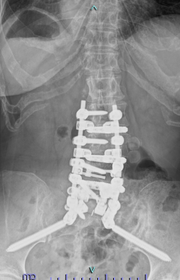

第2, 第3, 第4腰椎に前方への変性すべりを認めます。痛みのため背中を反って立てないことが分かります。MRIではいずれの椎間でも強い脊柱管狭窄が発生し、神経が圧迫されているのが分かります。

【術後】

スクリューとロッド、人工骨を使用した手術により腰椎の階段状変性すべりが整復され、痛みが改善したため腰を反って立つことが出来ています。第2腰椎の前方すべりは軽微であったため、金属は使わず除圧術のみに留めています。